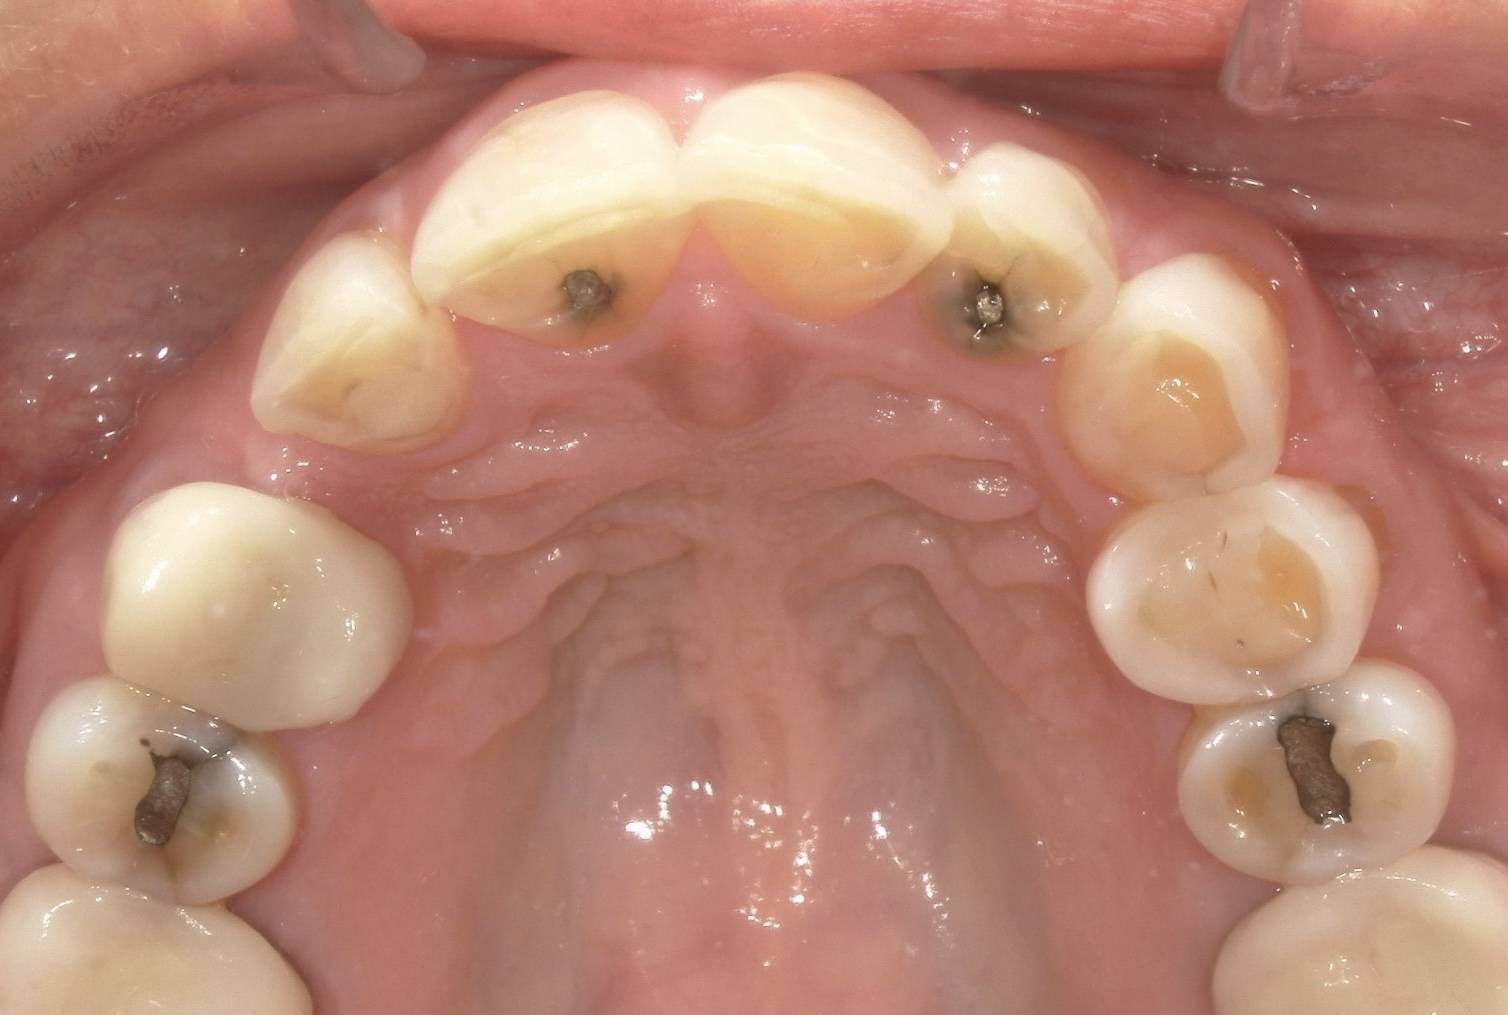

Many people still carry the “silver” fillings placed years ago, assuming they are harmless. Yet, these restorations, known as mercury amalgam fillings, contain roughly half mercury, a metal now recognized for its potential effects on human health and the environment. Over time, tiny amounts of vapor can be released through daily activities such as chewing or grinding teeth.

Silver fillings release mercury vapor continuously. Typical steady-state mercury release from a single filling is estimated at about 0.03 micrograms per day, although chewing and brushing can temporarily increase this amount. This exposure continues for years or decades.

Removing dental amalgam fillings without proper safety precautions can release high levels of mercury vapor, measuring approximately 15-20 micrograms per filling. This exposure can be up to ten times higher than daily mercury vapor release from intact fillings, occurring within minutes of removal.